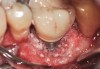

Problem: The implant is placed too facially, and there is significant labial gingival recession, contour change, and mucosal discoloration around the implant, abutment, and crown (Figure 3 and Figure 4). The implant attachment apparatus is intact and healthy, but the patient has a thin periodontal phenotype.

The following case report provides an example of this case scenario: A 28-year-old white female patient presented with her maxillary right lateral incisor significantly longer than the contralateral tooth following restoration of an existing crown that was 10 years old (Figure 3). The patient was dissatisfied with the esthetic appearance of the restoration due to the increased length, recession of the gingival tissues, and discoloration of the surrounding mucosa (Figure 4). Similar to case scenario No. 1, the first step in treatment was to decoronate the healthy implant by placing a flat surgical cover screw and employing a provisional resin-bonded-retained (RBR) prosthesis as a transitional fixed restoration (Figure 5 and Figure 6). The gingival augmentation in situ was allowed to take place for 2 to 3 weeks and was evaluated after that time (Figure 7).

Fig 3. A patient presented with a high smile line and midfacial recession of the maxillary right lateral incisor as evidenced by the increased tooth length compared with the contralateral lateral incisor.

Fig 4. Intraoral view of tooth No. 7 with the gingival zenith more apical than the adjacent central incisor and canine tooth.